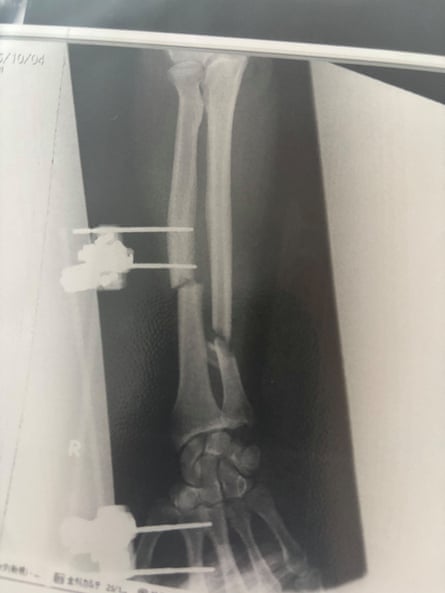

For New Zealander Billy Halloran, the attack only ended when the bear suddenly backed away. It was then that he looked at his injured arm. “It was way out of shape,” he says.

After a 40-minute drive, with no pain relief, Halloran was admitted to hospital, where he underwent emergency surgery to reconstruct his arm. One bone had been snapped in half, and the other broken into two segments.

“The doctors were impressed,” he says. “It was quite shocking to them.”